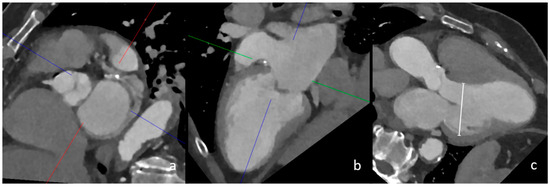

4.1. Left Ventricular Dilatation

4.5. Previous Myocardial Infarction